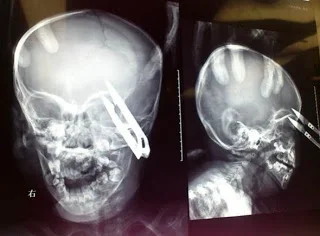

A

medula óssea é um tipo de tratamento para algumas doenças que afetam as

células do sangue, como leucemia e linfoma (Foto: Divulgação)